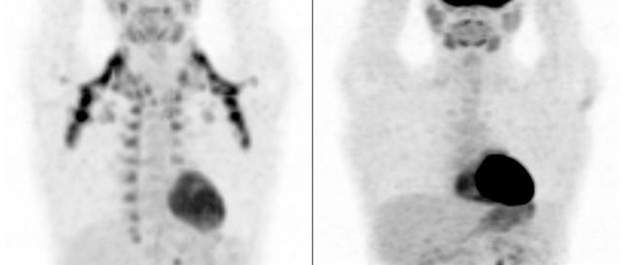

Las fracturas en remisión y los callos óseos pueden captar la FDG (fig. 4).